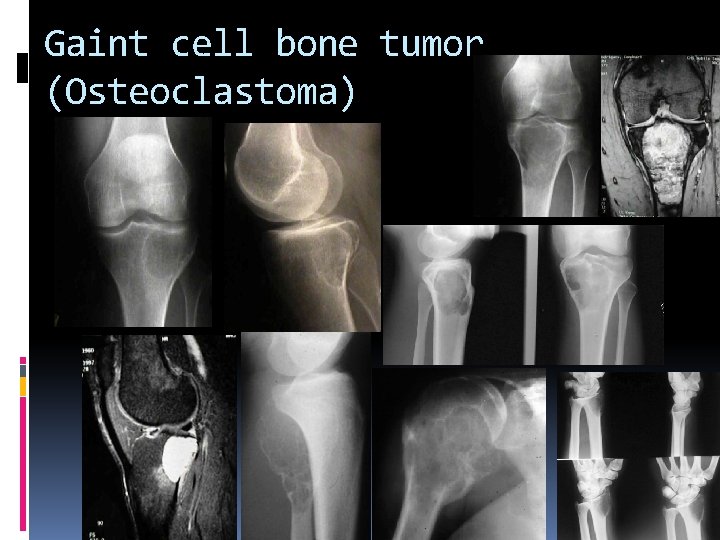

Gaint cell bone tumor (Osteoclastoma)